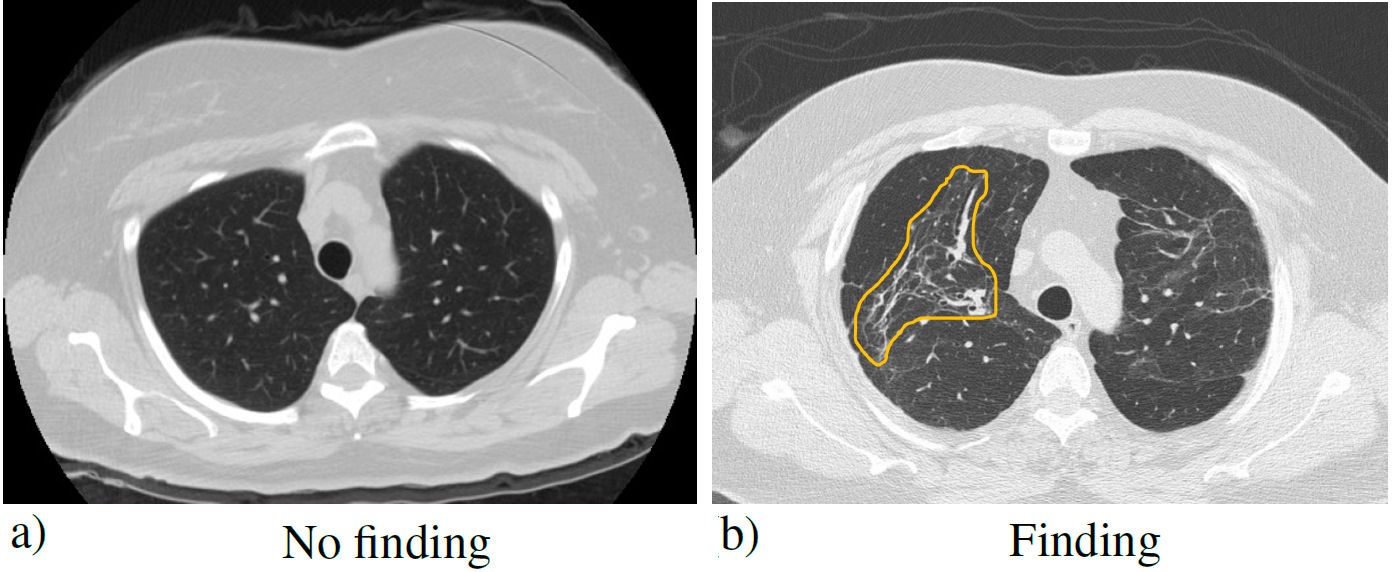

The data set used in the present investigation was provided by the Unidad Médica de Alta Especialidad No. 1 (High Specialty Medical Unit) of the Instituto Mexicano del Seguro Social (Mexican Institute of Social Security), T1-IMSS of León, Guanajuato, Mexico, from Mexican patients infected with COVID-19. The post-COVID diagnosis was made to 16 patients: approximately one year after their infections. The medical diagnosis was obtained from the imaging study, through computed tomography (CT) of the chest, which is more sensitive than conventional radiography, and for this reason, it was the main diagnostic method used in the pandemic [11]. In the tomography, two types of cases were observed: normal and abnormal. 57 CT images with postCOVID findings and 57 images without findings were obtained (symmetrical set). The most common findings were ground glass image, which can be translated into an acute inflammatory process and possibly represents immature fibrosis that can resolve or progress over time, and pulmonary fibrosis; mainly made up of findings such as architectural distortion, traction bronchiectasis, and cobblestone pattern. These conditions are usually undetectable on radiography, so tomography is more efficient. Axial CT slices of the patients were 0.5 mm, to detect these patterns. Figure 1 shows the two types of labels in the dataset.

FIGURE 1 Simple chest tomography with the pulmonary window in the axial section, where a) no finding is observed and b) a typical pattern of pulmonary fibrosis (distortion of the pulmonary architecture) derived from COVID-19 (yellow outline).